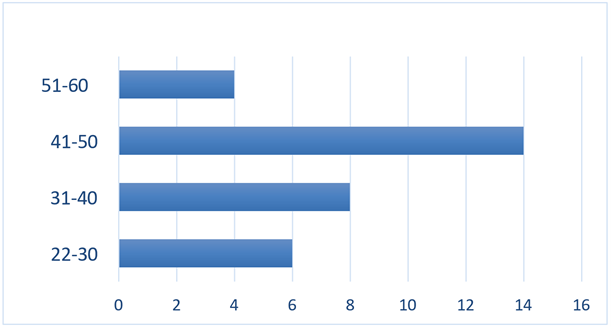

1/ Age distribution of patients: During the study period, we recorded 32 cases of urogenital tuberculosis. The mean age of our patients was 41 years, with extremes ranging from 22 to 60 years and a standard deviation of 7 years (Figure 1).

Figure 1: Distribution of patients by age.

The mean age in our study was 41 years, with extremes ranging from 22 to 60 years. This mean is tending to increase in our country, following the national BCG vaccination program, which protects the young population, as well as the insidious evolution of the disease and the aging of the population. The average age was 38 in a study by Benchekroun et al. in Rabat [6] and 34 in the study by Bennani et al. in Casablanca [7].